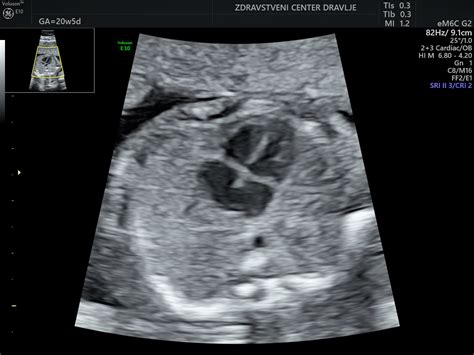

Možgani otroka postajajo vse bolj kompleksni in zaviti, kar se odraža v povečani možganski aktivnosti. Opazimo lahko že ustaljen ritem budnosti in spanja, čeprav se ta pogosto ne ujema z materinim. Otrok počasi začenja odpirati in zapirati oči, s čimer razlikuje med svetlobo in temo. Na njegovem jeziku se razvijajo prve okušalne brbončice, kar mu omogoča okušanje okusov v plodovnici, ki jo pije. Razvoj vida in okusa je tesno povezan z razvojem možganov. Proporcije otrokovega telesa postajajo vse bolj podobne proporcijam ob rojstvu; glava zdaj raste počasneje, da jo lahko preostanek telesa dohiteva. Zaradi pomanjkanja podkožne maščobe je koža na njegovem telesu še vedno nagubana, vendar se bo to z razvojem maščobnih celic spremenilo. Na ultrazvoku je mogoče opaziti, da dojenček že sesa svoj palec. Čuti lahko ritmične gibe, kot je kolcanje, ki se v tem tednu lahko pojavlja pogosteje.

V 27. tednu nosečnosti se boste verjetno vse pogosteje spraševali o spolu dojenčka. Z ultrazvokom je v tem tednu spol že mogoče določiti, saj so spolni organi skoraj povsem razviti. Vendar pa je natančnost odvisna od lege otroka in kakovosti ultrazvočne opreme.